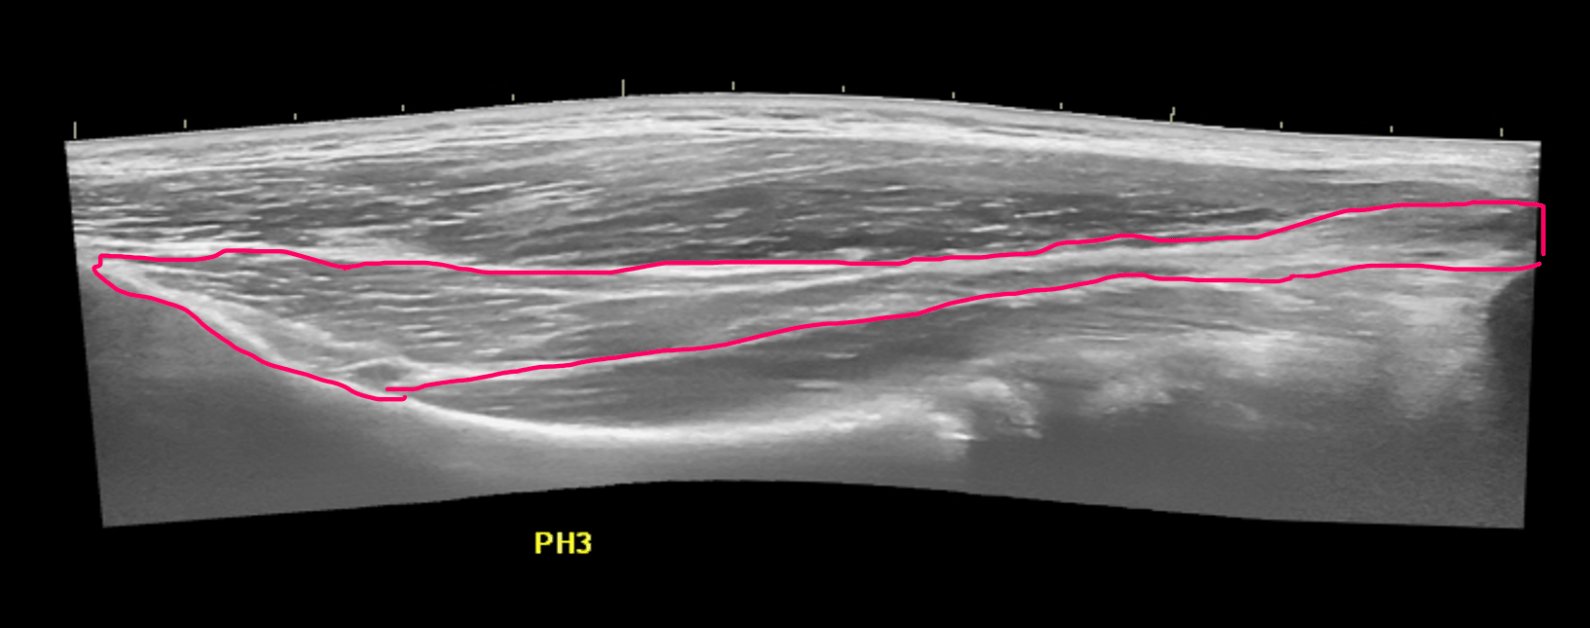

In this extended field of view image the red structure in this well known interval is one of 2 “leaders” for its muscle.

What is the long head biceps tendon?